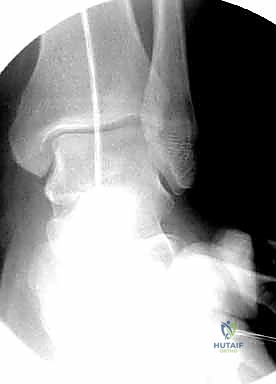

- الأشعة السينية (X-Rays): أخذ صور من زوايا متعددة (أمامي خلفي، وجانبي) لتحديد موقع الكسر ونوعه.

قبل بدء الجراحة، يتم رسم خطة دقيقة. يتم وضع المريض على طاولة العمليات المجهزة بأشعة (C-Arm) لضمان التصوير الفوري أثناء الجراحة.

المرحلة الخامسة: الإغلاق التجميلي

بعد التأكد التام من استقرار الكسر وحركة المفصل عن طريق الأشعة داخل غرفة العمليات، يتم إغلاق الجرح بطبقات متعددة باستخدام خيوط تجميلية لتقليل الندبات، ووضع أنبوب تصريف (Drain) لمنع تجمع الدم.